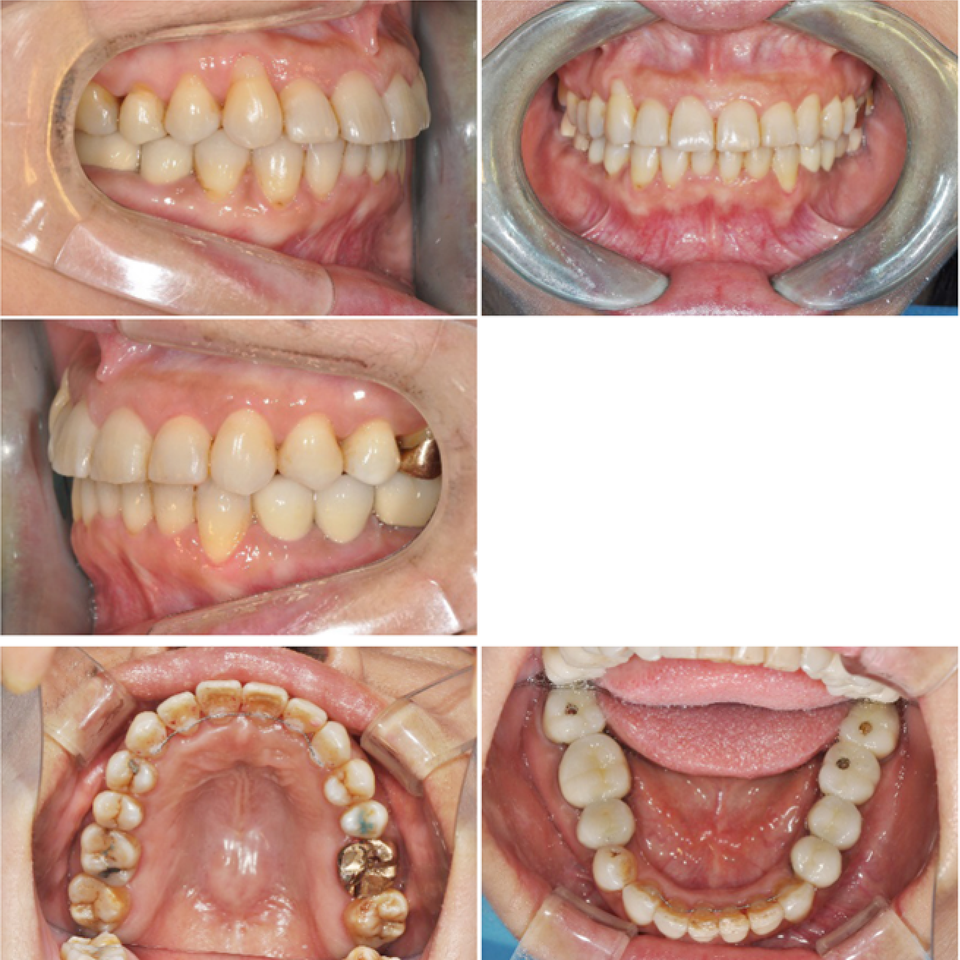

이 환자는 하악우측 제2대구치와 좌측 제1,2대구치가 결손된 환자로 하악 양측 distal cantilever 보철물 하방의 식편압입과 잇몸염증을 주소로 내원하였습니다. 또한 전치부의 crowding을 해결하기 위한 전악교정치료를 원하셨습니다.

하악구치의 cantilever 보철물을 제거하고 temporary crown으로 수복하여 bracket을 부착하였으며 결손부위는 일단 놔둔 상태에서 교정치료를 진행하였습니다.

전치부 decrowding의 영향을 고려하더라도 상하악 전치부의 flare와 동요도가 발생하였는데 이는 대구치부위 posterior support의 부재의 영향이 큽니다.

상악에서 miniscrew를 이용한 2mm 정도의 total arch distalization을 계획하였으므로 상응하는 최종교합형성을 고려하여 하악 대구치부에 임플란트식립을 진행하였고 구치부 support의 조기확립을 위해 temporary crown을 이용한 임플란트 상부보철 진행후 하악치열의 후방이동을 진행하기로 하였습니다.

하악임플란트상부보철물에 tube를 부착하되 tube slot에 각형호선이 가급적 passive 하게 들어가도록 보철물의 모양과 tube 부착위치를 조절하였습니다. 계획된 후방이동량만큼 임플란트 보철물과 전방 자연치간의 space를 형성하여 전방치열을 후방견인하였습니다.

마무리된 교합은 초진시에 동일하게 양측 Class 1 교합으로 마무리하였으며 측모두 부방사선 사진에서 보듯 교정중 발생했던 전치의 flare가 개선되었습니다.